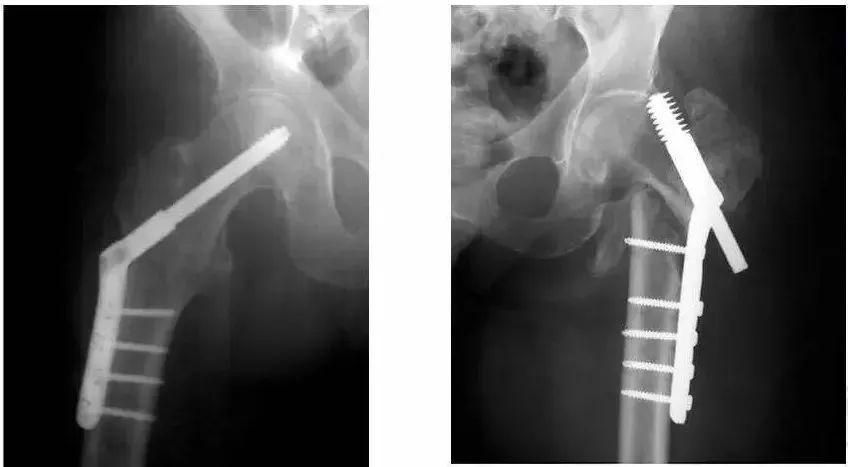

1、内固定。根据骨折情况、骨质情况选择髓内钉、钢板或螺丝钉内固定。

1、内固定:适合骨质良好的粗隆部骨折。

优点:骨折愈合后恢复到骨折前的解剖状态,闭合髓内钉技术创伤小。

缺点:骨质疏松患者内固定把持力不足,容易出现内固定剪切失效;即使固定牢固,也不能早期负重行走,恢复比较慢。

粗隆间骨折,骨质疏松,把持力不良,钉板固定,螺钉切割失败。